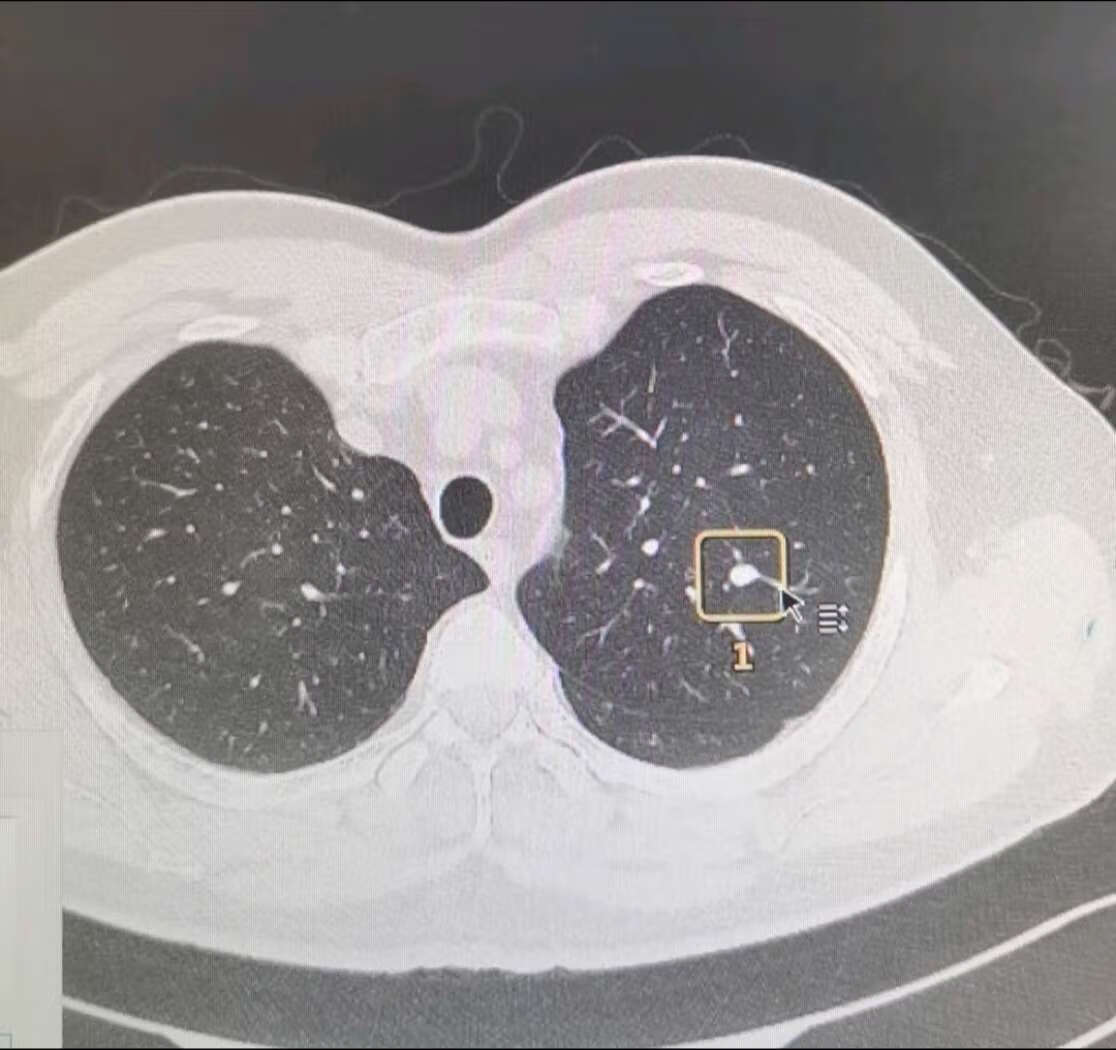

罕见病例反复低烧长达1个多月伴肺结节各种检查都找不到发烧的原因

你知道多发肺结节长什么样吗?

肺结节大小的分类